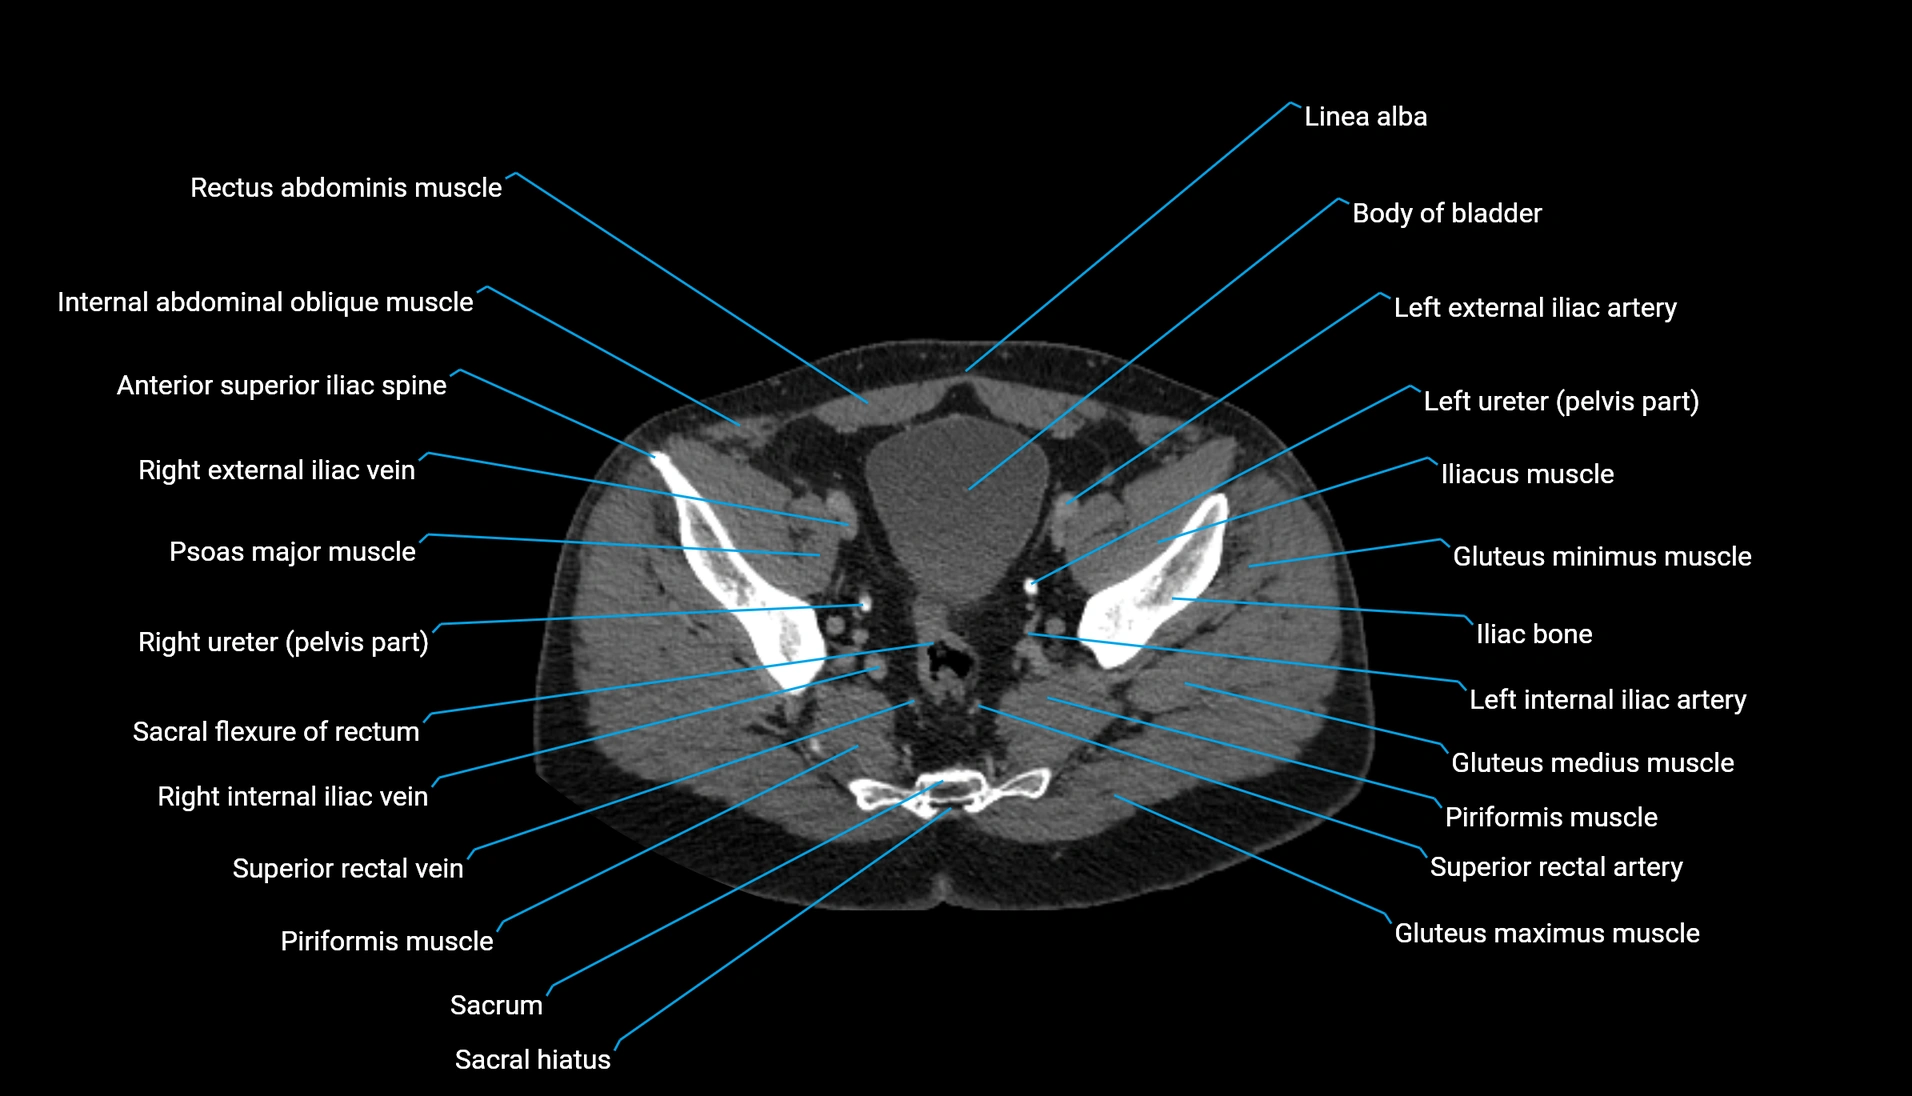

CT Appearance

Non-contrast CT:

-

Demonstrates cortical bone of acetabular rim in excellent detail

Detects fractures, dysplasia, retroversion, or bony overcoverage (pincer impingement)

3D reconstructions used in preoperative hip surgery planning

CT VRT 3D image

CT image